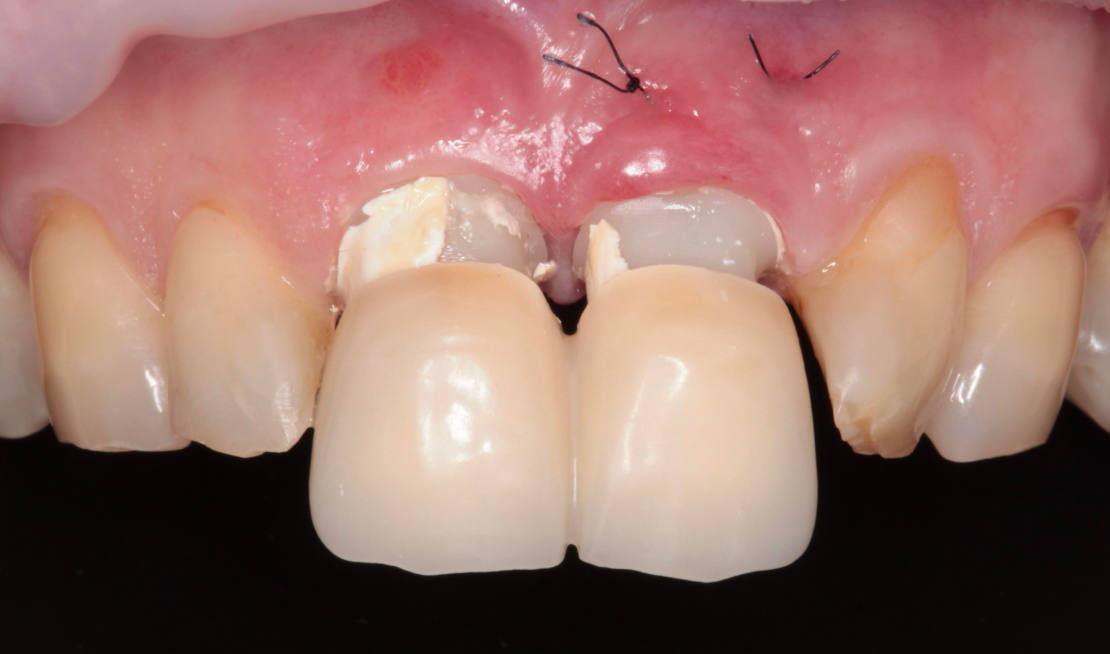

Vďaka týmto postupom bola operácia veľmi rýchla a pacientka odišla z ordinácie plne rehabilitovaná. Minimálne invazívnym spôsobom boli extrahované horné jednotky (obr. 6).

Následne sme použili protokol vŕtania a zavedenia implantátov cez šablónu (obr. 7, 8), na ktorej sme mali orientačné body pre správne napolohovanie implantátov, abutmentov a koruniek (obr. 9–14).